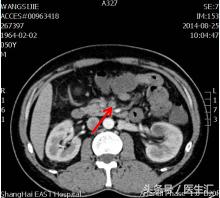

第7天清晨2:00夜班医生查体全腹部平软,但是上腹部有一点点轻压痛,无反跳痛,麦氏点无压痛,夜班医师给与654-2解痉处理,但是效果还是不满意。所以做了一个中上腹CT平扫示:肠系膜上动、静脉周围渗出性改变,建议增强扫描。第7天早上10:00做中上腹增强CT示:肠系膜上动脉内低密度影,考虑附壁血栓形成,局部管腔重度狭窄。这个时候这个患者的诊断应该来说已经很明确了。于是请了相关科室的医生进行会诊,决定进行经皮选择性肠系膜动脉造影+肠系膜动脉溶栓术。患者溶栓导管行脉冲式注射尿激酶溶栓,患者术后24h出现便血4次,200ml/次。